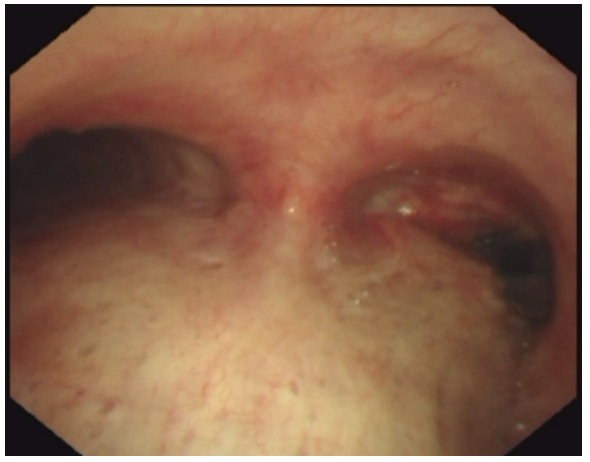

支气管镜见右主支气管开口新生物堵塞伴管腔狭窄(狭窄约80%),表面充血易出血,初步考虑中心气道狭窄分级:右主支气管,狭窄程度:Ⅳ级(76-90%)狭窄长度:~2cm,结合患者肿瘤病史以及移植后长期抗排异治疗,考虑新生物为肺癌复发或感染性病变可能,经验性予莫西沙星针0.4 qd抗感染,并行支气管镜介入治疗清除病变组织以及超声支气管镜引导下经支气管针吸活检(EBUS-TBNA)术。

image.png

图4 2024-12-30胸部CT示右主支气管结节(红色箭头),纵隔淋巴结肿大;气管镜示右主支气管开口新生物堵塞伴管腔狭窄;超声支气管镜下7组纵隔淋巴结TBNA术